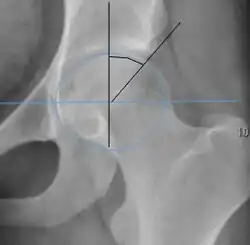

| Alpha angle | ![]() |

Degree of bulging of the femoral head-neck junction: In normal conditions there is a symmetric concave contour at the junction of the femoral head and neck. Loss of this concavity or bone bulging may lead to cam type impingement. The degree of this deformity can be measured by the alpha angle. Although it can be measured in the cross-lateral view, the 45° Dunn view is considered more sensitive and the frog leg view more specific in determining pathologic values. |

|

MRI imaging may follow, particularly if there is no specific evidence on radiographs, producing a three-dimensional reconstruction of the joint for better definition, to evaluate the hip cartilage, or measure hip socket angles (e.g. the alpha-angle as described by Nötzli[22] in 2-D and by Siebenrock in 3-D[23]). MR arthrogram had been used in the past, as it was more sensitive for picking up soft tissue lesions; however, due to improvement in technology, MRI is now considered comparable for picking up such lesions.[6] CT is not usually used due to radiation exposure and no benefit above MRI.[6] It is possible to perform dynamic simulation of hip motion with CT or MRI[24][25] assisting to establish whether, where, and to what extent, impingement is occurring.